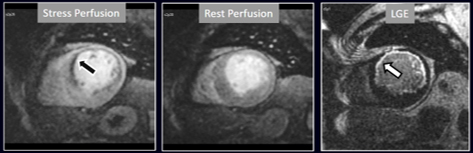

The most immediate and commonest method of analysis is the visual detection of a distinctive deficient increase in signal intensity of a region of the left ventricular myocardium during the first passage of a CA bolus under vasodilatory conditions lasting for at least 3 consecutive frames of the sequence. This perfusion defect should not be present at rest and should not correspond to an area of previous MI. The detection of such a defect is assumed to be due to a reduction in CFR of this territory which, when attributed to a particular coronary artery [39], allows for the conclusion of the presence of a significant epicardial stenosis in the vessel (Fig. 6).

Fig. 6.Single-vessel perfusion defect. Extensive subendocardial perfusion defect at the antero-septal region (arrow, on the upper left panel) not present at rest, in a region without LGE (lower left panel). Angiography proves this defect to be due to a tight stenosis of the LAD coronary artery (arrow, on the lower right panel).